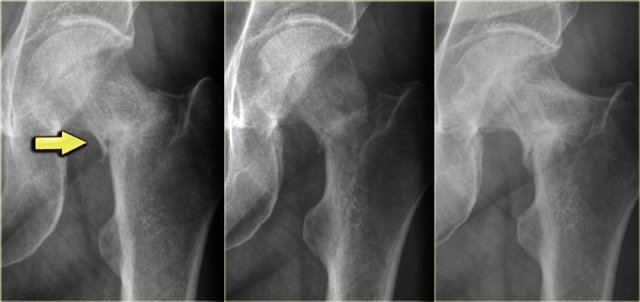

Here a lesion in the epiphysis, which was the result of post-traumatic osteonecrosis.

In the epiphysis we use the term avascular necrosis and not bone infarction.